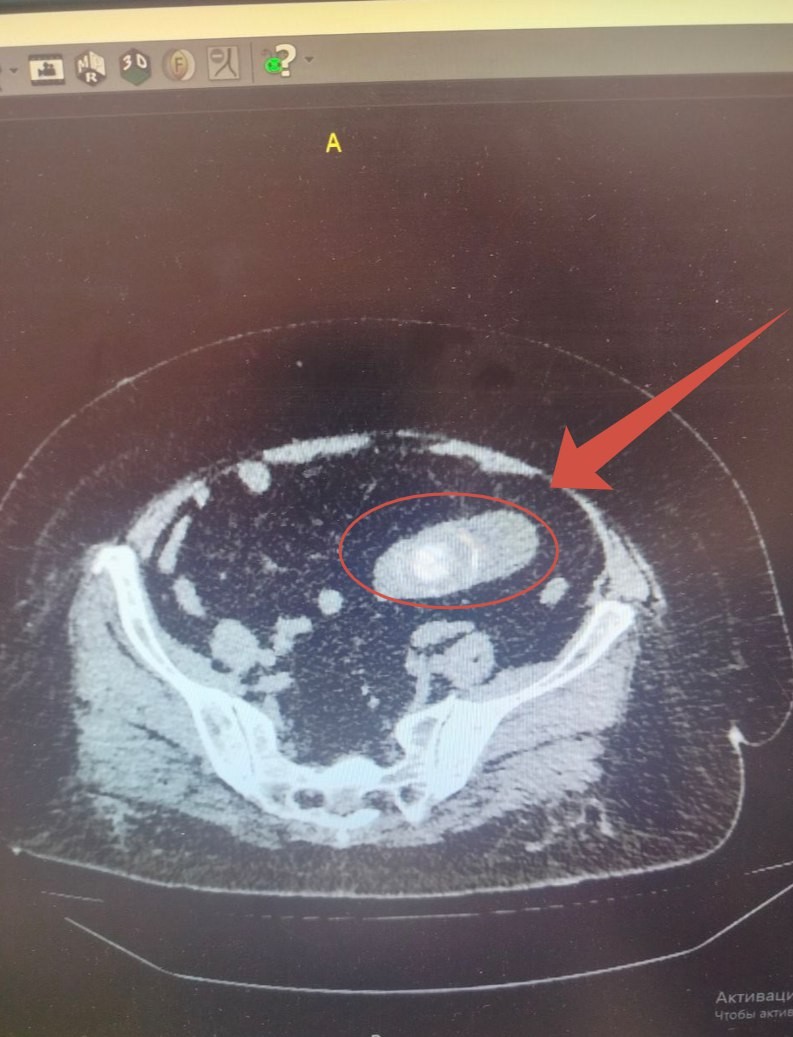

Но после операции появились сильные боли в животе и неукротимая рвота. РКТ обследование показало шокирующую картину: огромный камень в кишечнике вызвал острую кишечную непроходимость.

В ходе экстренной операции хирурги обнаружили, что камень мигрировал из желчного пузыря в кишечник через свищ. Именно он, а не почечный камень, и стал виновником тяжелого состояния.

Хирурги удалили гигантский конкремент размером 6 на 4 см и восстановили работу кишечника.